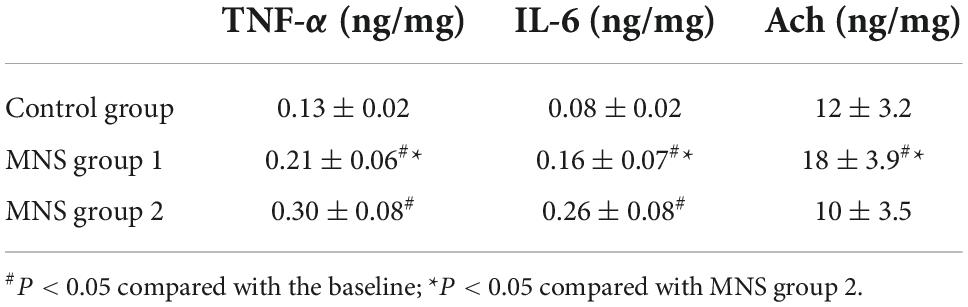

As highlighted in Table 4, the concentrations of TNF-α and IL-6 in the peri-infarct zone of LV tissues were significantly higher in the MNS group 1 (TNF-α: 0.21 ± 0.06 ng/mg vs. 0.13 ± 0.02 ng/mg, P = 0.02; IL-6: 0.16 ± 0.07 ng/mg vs. 0.08 ± 0.02 ng/mg, P = 0.03) and the MNS group 2 dogs (TNF-α: 0.30 ± 0.08 ng/mg vs. 0.13 ± 0.02 ng/mg, P < 0.01; IL-6: 0.26 ± 0.08 ng/mg vs. 0.08 ± 0.02 ng/mg, P < 0.01) than in the control group dogs. However, compared to the MNS group 2, the concentrations of TNF-α (0.21 ± 0.06 ng/mg vs. 0.30 ± 0.08 ng/mg, P = 0.04) and IL-6 (0.16 ± 0.07 ng/mg vs. 0.26 ± 0.08 ng/mg, P = 0.04) were lower in the MNS group 1 dogs, whereas the levels of Ach were higher in the MNS group 1 dogs than that in the control (18 ± 3.9 ng/mg vs. 12 ± 3.2 ng/mg, P = 0.02) and MNS group 2 dogs (18 ± 3.9 ng/mg vs. 10 ± 3.5 ng/mg, P < 0.01).

Table 4. Levels of the tumor necrosis factor-alpha (TNF-α), interleukin-6 (IL-6), and acetylcholine (Ach) in the left ventricular tissues in control group, median nerve stimulation (MNS) group 1, and MNS group 2.